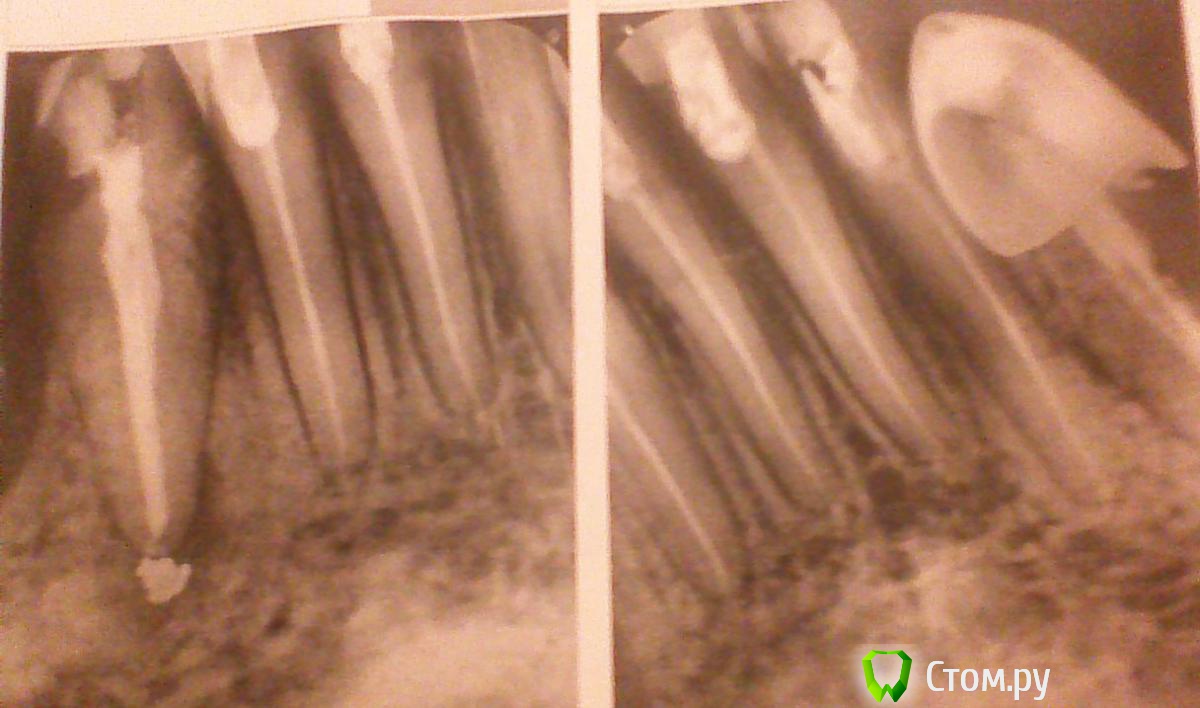

Mancini Опубликовано 2 октября, 2014 Поделиться Опубликовано 2 октября, 2014 (изменено) Здравствуйте, уважаемые стоматологи! Требуется коллективный разум для определения оптимального плана лечения (имплантология) в следующем случае. Дано: Женщина, 61 год, врач (не стоматолог), к.м.н. Все зубы депульпированы. На нижней правой 3-ке киста, которая сейчас находится в процессе пролечивания, результат лечения неопределен (зуб пол временной пломбой). Рот проблемный по крайней мере последние 25 лет, в нем регулярно что-то болит. Зубы и десны болят при малейшем охлаждении (холод, сырость, простуда и т.д.). Имеется остеопороз, парадонтит, дисфункция ВНЧС, компенсированный гипотериоз, низкий болевой порог. Сильно измененный прикус. Присутствуют мышечные спазмы лица, выражающиеся в виде боли, которая переходит с одной четверти рта на другую, потом на третью и четвёртую, далее снова по кругу. Спазмический характер болей предположили в институте стоматологии на ул. Вучетича (Москва), там же категорически отвергли предположение о том, что боли вызваны воспалением тройничного нерва. 3 года назад после удаления нижних 4-ки и 5-ки полгода была на больничном, т.к. раны не заживали, гноились и т.д., после лечения антибиотиками был выявлен кандидоз (брали посев). Последние 3 года имею съемное протезирование на 4-7 зубы нижней челюсти с обеих сторон. Сменила несколько протезов, т.к. они постоянно ломаются. Было 2 нейлоновых протеза – пришли в негодность, сейчас имею пластмассовый, от которого постоянно отлетают крючки. С пластмассовым протезом 1 раз в месяц (!) хожу на перебазировку – по словам врача, уходит десна. В итоге съемными протезами пользуюсь от случая к случаю, что, конечно, ухудшает и без того печальную ситуацию во рту. В настоящее время ищу вариант протезирования нижней челюсти на имплантатах (в 2010 г. в нескольких клиниках почему-то сказали, что импланты невозможны) после полного удаления зубов снизу. Предложено 2 концепции: Удалить все зубы внизу, ждать 2 недели заживления, сделать временный съемный пластмассовый протез, дождаться стабилизации кости после удаления (~ 6 мес.), сделать постоянный съемный пластмассовый протез, начинать обсуждать (только обсуждать!) возможность наращивания кости и последующей имплантации. При неудаче в имплантации – пожизненная съёмная пластмасса. Весь процесс должен занять 1,5 – 2 года. Провести имплантацию в течении 3-4 мес. на следующих условиях: импланты Nobel Replace Groovy в количестве 4 штук устанавливаются одновременно с удалением нижних зубов, при этом импланты ставятся в центральной части челюсти, там где не ушла кость; сразу ставится временная конструкция; постоянное протезирование осуществляется пластиковым протезом на титановой балке Procera (как я поняла, протез как бы условно-съемный), который нуждается в профилактических работах у стоматолога (чистка и прочее) 1 раз в 6 мес. Вторая концепция протезирования предполагает ставить импланты сразу после удаления, не дожидаясь, пока уйдет кость, как это случилось в области 4-7 зубов, где сейчас используется съемный протез. При этом моя ситуация в целом оценивается как обычный штатный случай для имплантации, врач считает, что уходящая кость в районе 5-7 зубов, уходящая десна, из-за которой сейчас ежемесячно перебазируют съемную конструкцию, заживление лунки после удаление в теч 6 мес, имевшее место в прошлом, остеопороз и спазмы не создадут препятствий. Более того, в результате лечения многие эти проблемы должны уйти. В связи с этим прошу ответить на вопросы: Возможно ли протезирование на имплантах в моем случае с учетом состояния кости и уходящих десен по схеме 2-го варианта? Действительно можно обойтись без костной пластики, установив 4 импланта на месте 33-43 зубов? Установка имплантов одновременно с удалением – правильное решение с учетом состояния кости, десны и кисты на правой 3-ке? По вопросу протеза – пластик на титановой пластине будет нормален в эксплуатации, не будет проблем с деснами? Буду признательна за рекомендации врача (врачей) для проведения лечения (в соответствующей теме запрос оставила) и ориентацию по ценам (если возможно). Прилагаю снимки:1. панорамный;2. прицельные зубов нижней челюсти. Заранее спасибо. Изменено 2 октября, 2014 пользователем Mancini Ссылка на комментарий

Mancini Опубликовано 3 октября, 2014 Автор Поделиться Опубликовано 3 октября, 2014 Ваша позиция понятна. Видимо, моих возможностей не хватает для изложения комплексной сложной ситуации в двух предложениях. Переформулирую вопросы, возможно, так будет лучше: 1. Возможно ли протезирование на имплантах в моем случае на нижнюю челюсть (случай представлен на снимках)?2. Требуется ли костная пластика перед установкой имплантов?3. Следует ли соглашаться на установку имплантов непосредственно после удаления зубов нижней челюсти?4. От предложений базальной имплантации следует отказываться сразу?5. Срок службы устанавливаемого на импланты пластикового протеза на титановой балке составляет 2-3 года или другой срок?6. Возможно и разумно ли в данной ситуации, на ваш взгляд, вместо имплантов применить мостовидную конструкцию на 33-43 зубы и съемную на концы? Продолжаю надеяться на компетентные профессиональные мнения по существу ситуации.Буду очень признательна за любые предложения по плану лечения. Ссылка на комментарий

Bier Опубликовано 5 октября, 2014 Поделиться Опубликовано 5 октября, 2014 1. Возможно.2. Либо с транспозицией нерва либо с костной пластикой в боковых отделах, либо по концепции все на 4х, с установкой имплантатов только в переднем отделе н.ч.3. Это возможный вариант, но требует дополнительного обследования (Комп Томография)4. однозначно да.5. Если это условно-съемный протез на балке, то считается, что раз в 3-5 лет пластиковую часть надо менять на новую.6. Съемный всегда хуже несъемного, к тому же он вызовет дополнительную атрофию костной ткани. 1 Ссылка на комментарий